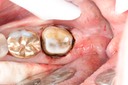

Kyle Chock #19 pre-op